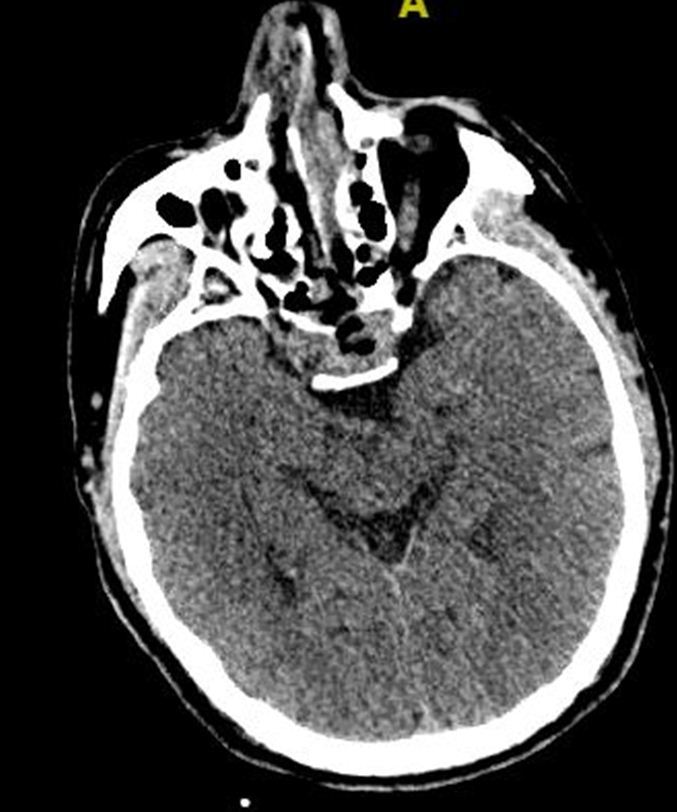

患者为中年患者,因头痛伴视物模糊半年起来就诊,鞍区增强MRI示:鞍区占位性病变,肿瘤大小约2.5cm,肿瘤突破鞍隔向上生长,顶部偏向右侧,视交叉受压明显,两侧侵犯海绵窦。T1WI为等信号,T2WI为混杂等信号,明显强化。复旦大学附属肿瘤医院神经外科高阳

术前磁共振图像: